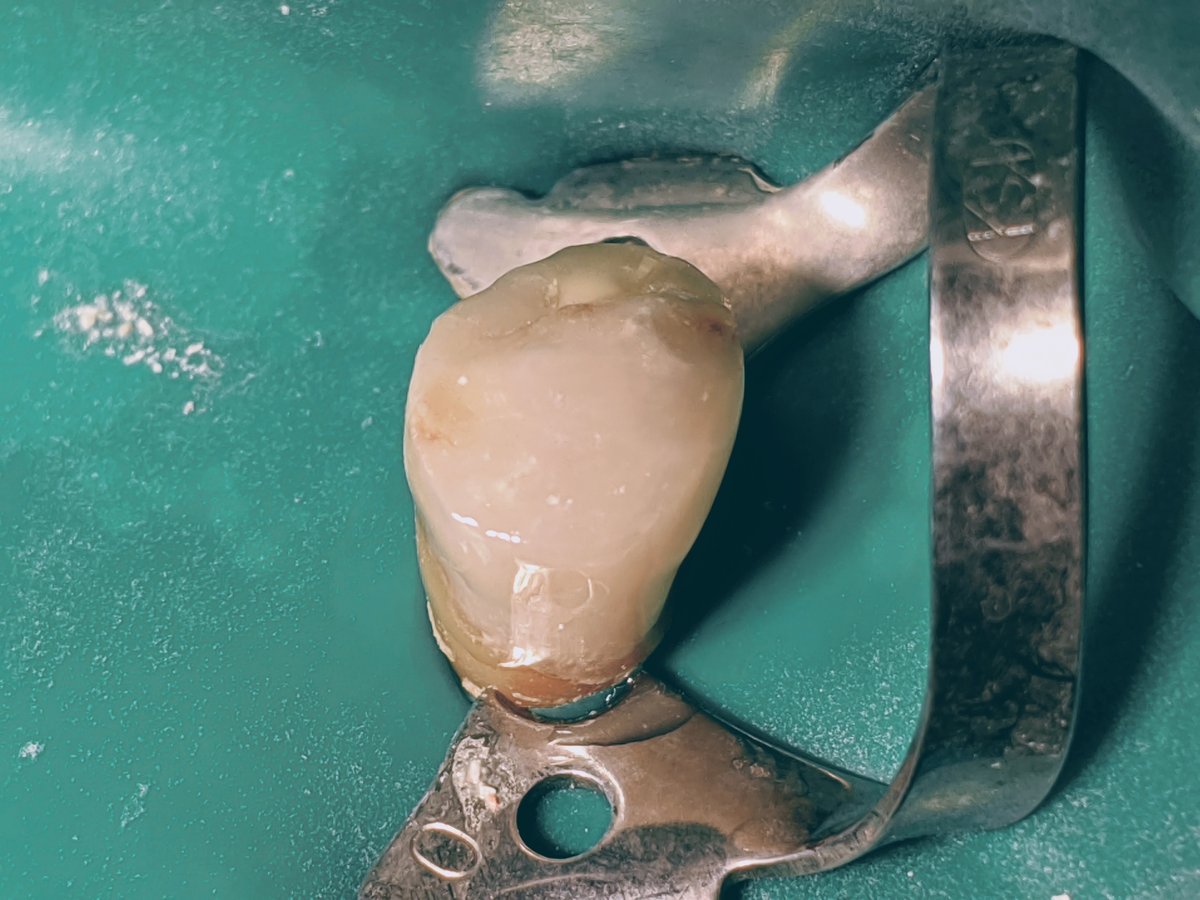

Der Parapost ist einzementiert, zwei Schraubenstifte im Restdentin gesetzt. Der Zahn ist mit Kofferdam isoliert.

Trockene Arbeitsbedingungen sind Voraussetzung für eine gute Haftung des Komposits, ob mit oder ohne Kofferdam.